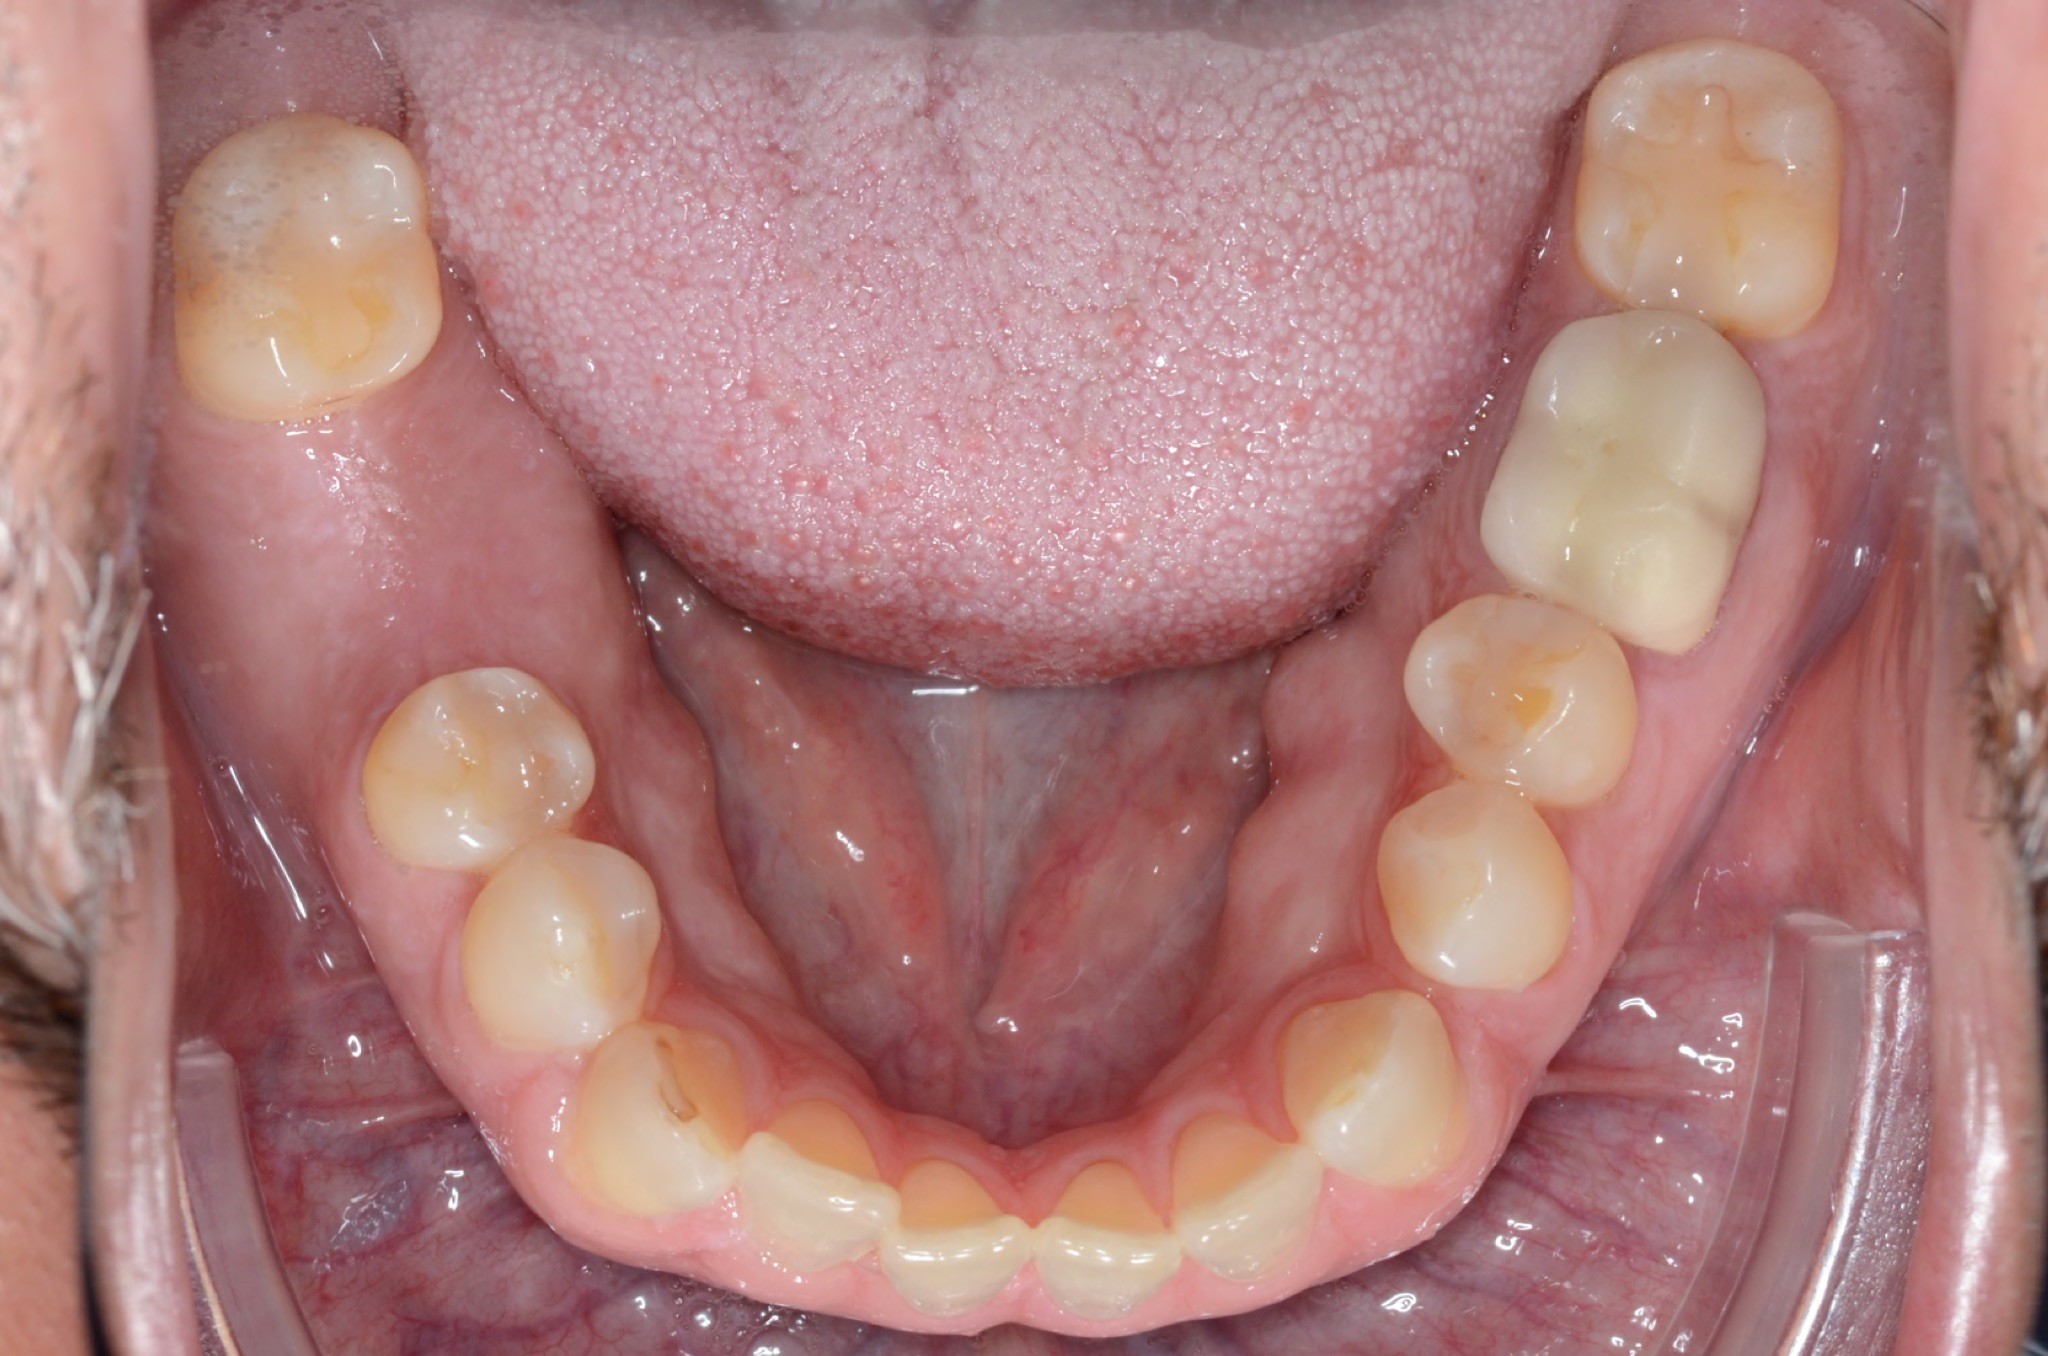

Initial treatment

INTRAORAL